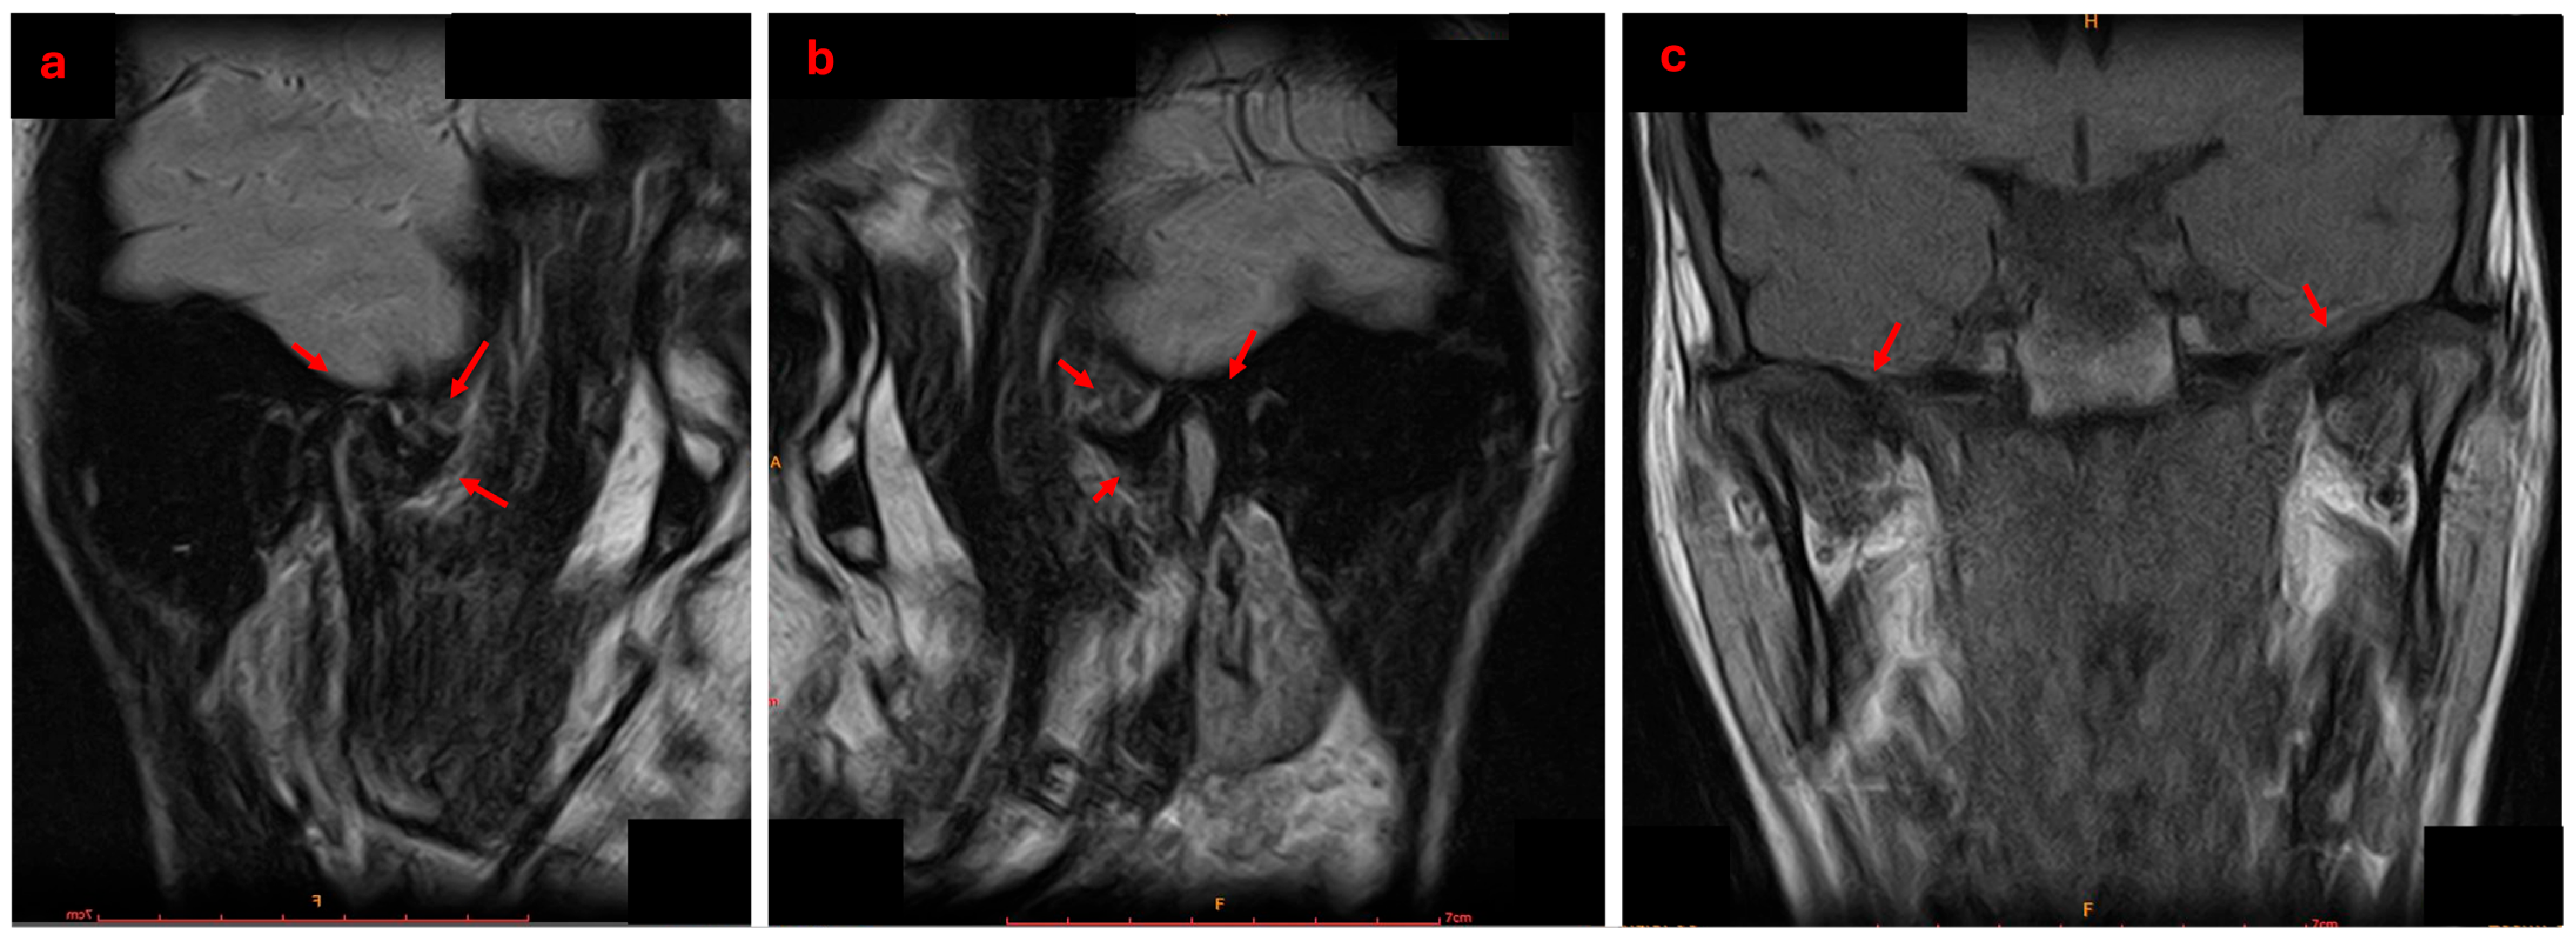

2.4. Diagnosis and Treatment Planning

- Di Paolo, C.; D’Ambrosio, F.; Panti, F.; Papa, M.; Mancini, P. The condyle-fossa relationship in temporomandibular disorders. Considerations on the pathogenetic role of the disc. Minerva Stomatol. 2006, 55, 409–422. [Google Scholar]

- Hasan, N.M.A.; Abdelrahman, T.E.F. MRI evaluation of TMJ internal derangement: Degree of anterior disc displacement correlated with other TMJ soft tissue and osseous abnormalities. Egypt. J. Radiol. Nucl. Med. 2014, 45, 735–744. [Google Scholar] [CrossRef]